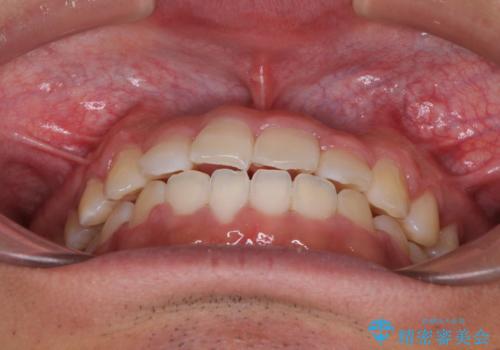

今後はすり減ってしまった歯の形をセラミッククラウンで改善したいとのことで、クロスバイトが改善し咬みやすくなった時点で装置を外すこととしました。

1年で治療を終えることができ、患者様には大変満足していただきました。